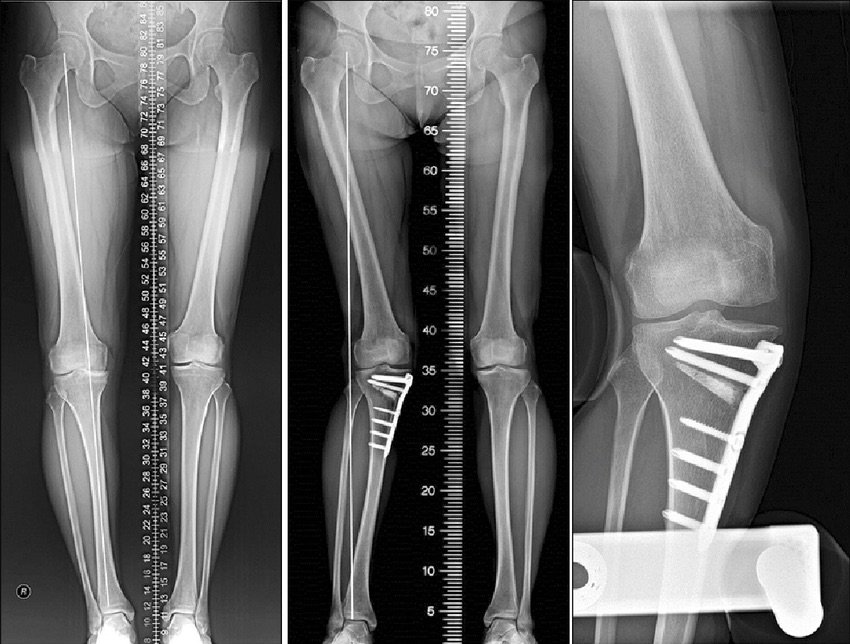

If OA is limited to one compartment, unicompartmental knee arthroplasty or unloading osteotomy (HTO) can be considered. They are recommended in young and active patients in regard to the risks and limited durability of total knee replacement.